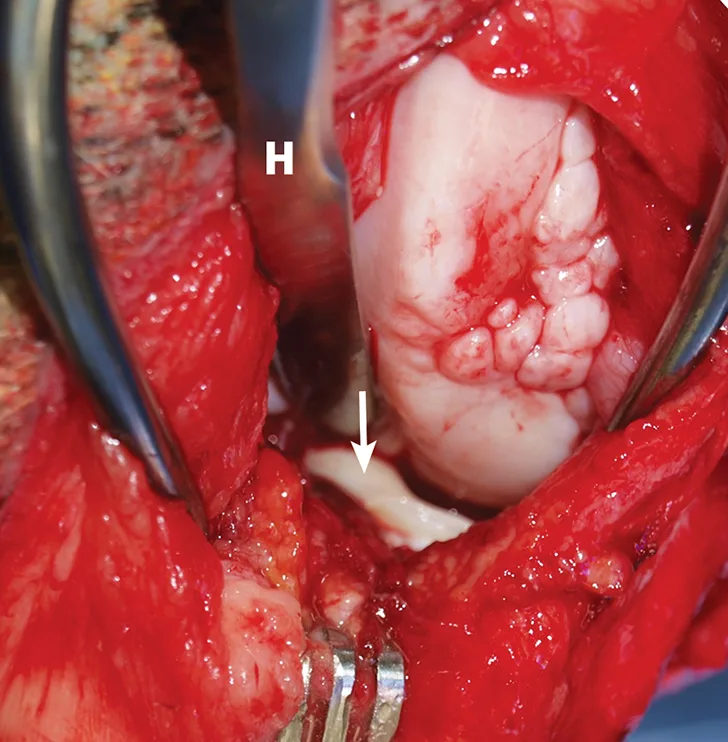

Intraoperative image with close-up of torn medial meniscus.

FIGURE 3

Intraoperative image demonstrating identification of medial meniscal tears by craniomedial arthrotomy in the dog in Figure 2. A Hohmann retractor (H) has been placed to allow inspection of the caudal joint space. The caudal pole of the medial meniscus has sustained a bucket handle tear and is flipped cranially (arrow).